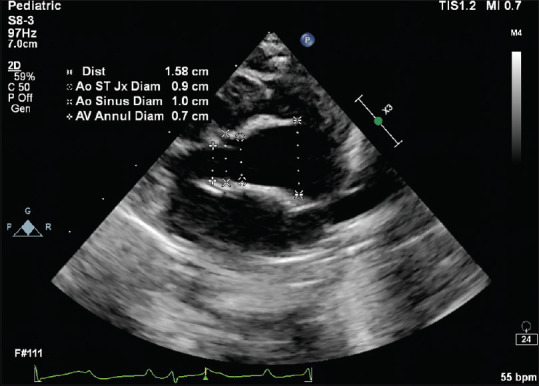

Ascending aorta dilatation has been reported in some cases of congenital complete heart block (CHB). Although maternal autoantibodies are implicated in the causation, the exact mechanism, significance, and management are not fully understood. In this report, we describe dilated ascending aorta in two neonates with congenital CHB and their short-term follow-up results.